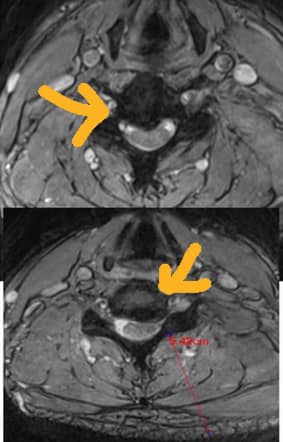

#頸椎整合中醫微創療法

治療:4/21~5/30(八次)

效果顯著,麻痛大幅度減輕。

先說結論!嚴重頸椎壓迫特別是中老年人,如果發現四肢已經開始僵硬或行動不良,很像失速列車裡面那種殭屍走路,如果是這種患者,強烈建議給神經外科手術!但至於是否會完全恢復呢?答案是很困難,頸部脊髓MRI如果嚴重壓迫病變,這表示頸脊髓發生不可逆之病變,這類患者症狀當然只有進步而無法完全復原,問題是很多中老年人很長期依賴止痛藥跟推拿,通常這種患者來診都已經很嚴重了,能夠恢復到免強日常生活自理都很不錯了